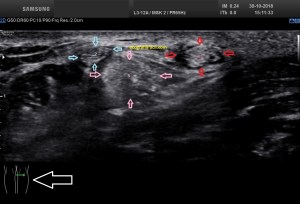

En la imagen 3 ves una imagen de un lipoma, mide 7 cms, la huella de la sonda mide 5cms, la «panoramic view» posee una regla centimetrada que sigue el contorno de la imagen, justo en la profundidad de la misma y lo marca la flecha amarilla. La profundidad la marca la flecha roja y la flecha blanca marca el rango centimetral de los 5cms, fíjate que la línea blanca es ligeramente mayor cada 5 cms. Sirve de referencia, como en la imagen 4 donde ves una colección en el glúteo de más de 10 cms.